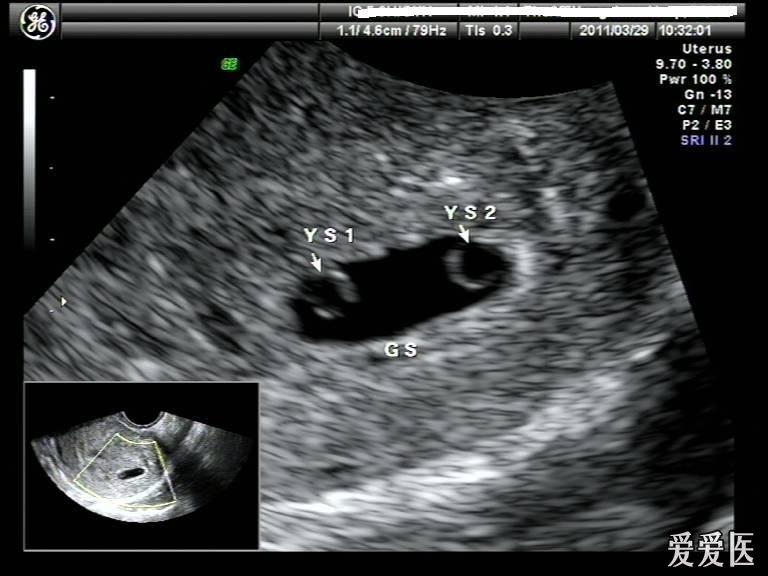

双胎超声图片

双胎超声图片,双胎图片

2011-14双胞胎(赏析 超声医学讨论版 爱爱医医学论坛